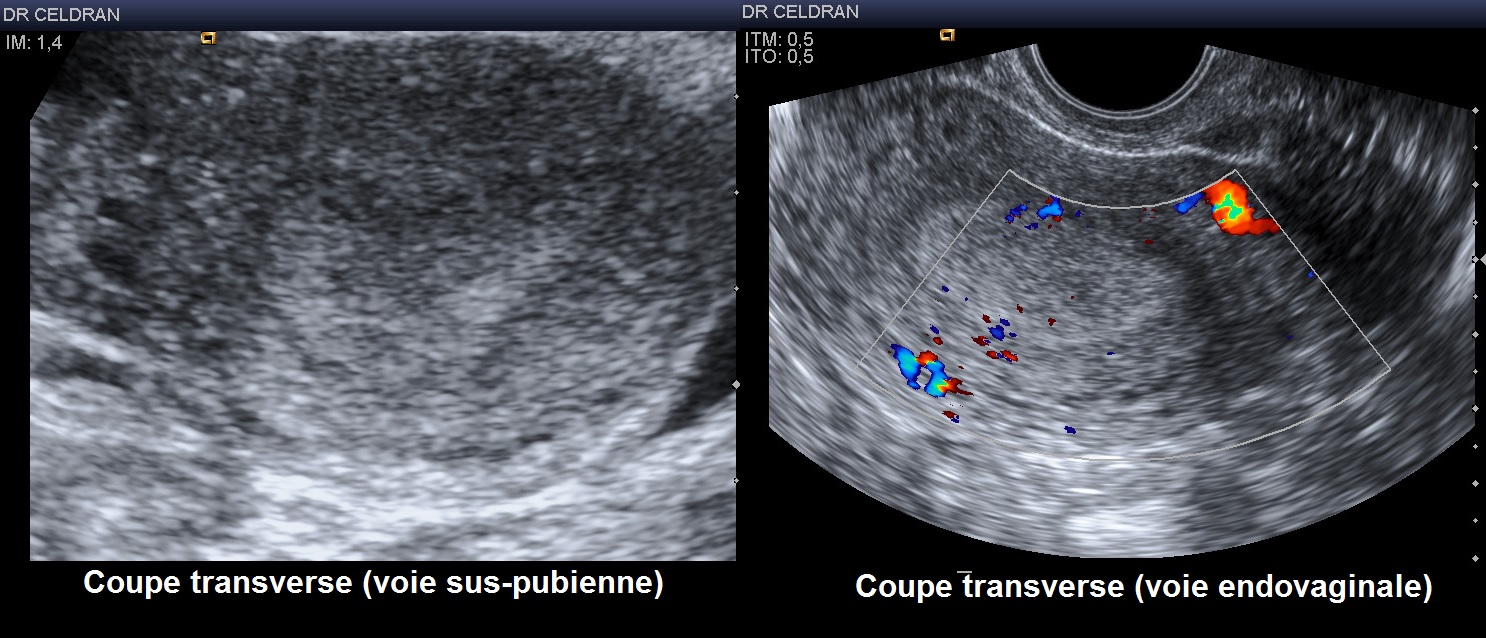

Une biopsie en cabinet a pour résultat : lambeaux d'endomètre atrophique sans atypies Et quand tu dis que le cancer n'est pas forcément déclaré, sache que bcp de cancers sont silencieux et non douloureux. L'exploration échographique de l'endomètre chez les femmes ménopausées et interprétation des résultats en fonction de l'épaisseur de l'endomètre et la présence ou non d'un traitement hormonal substitutif